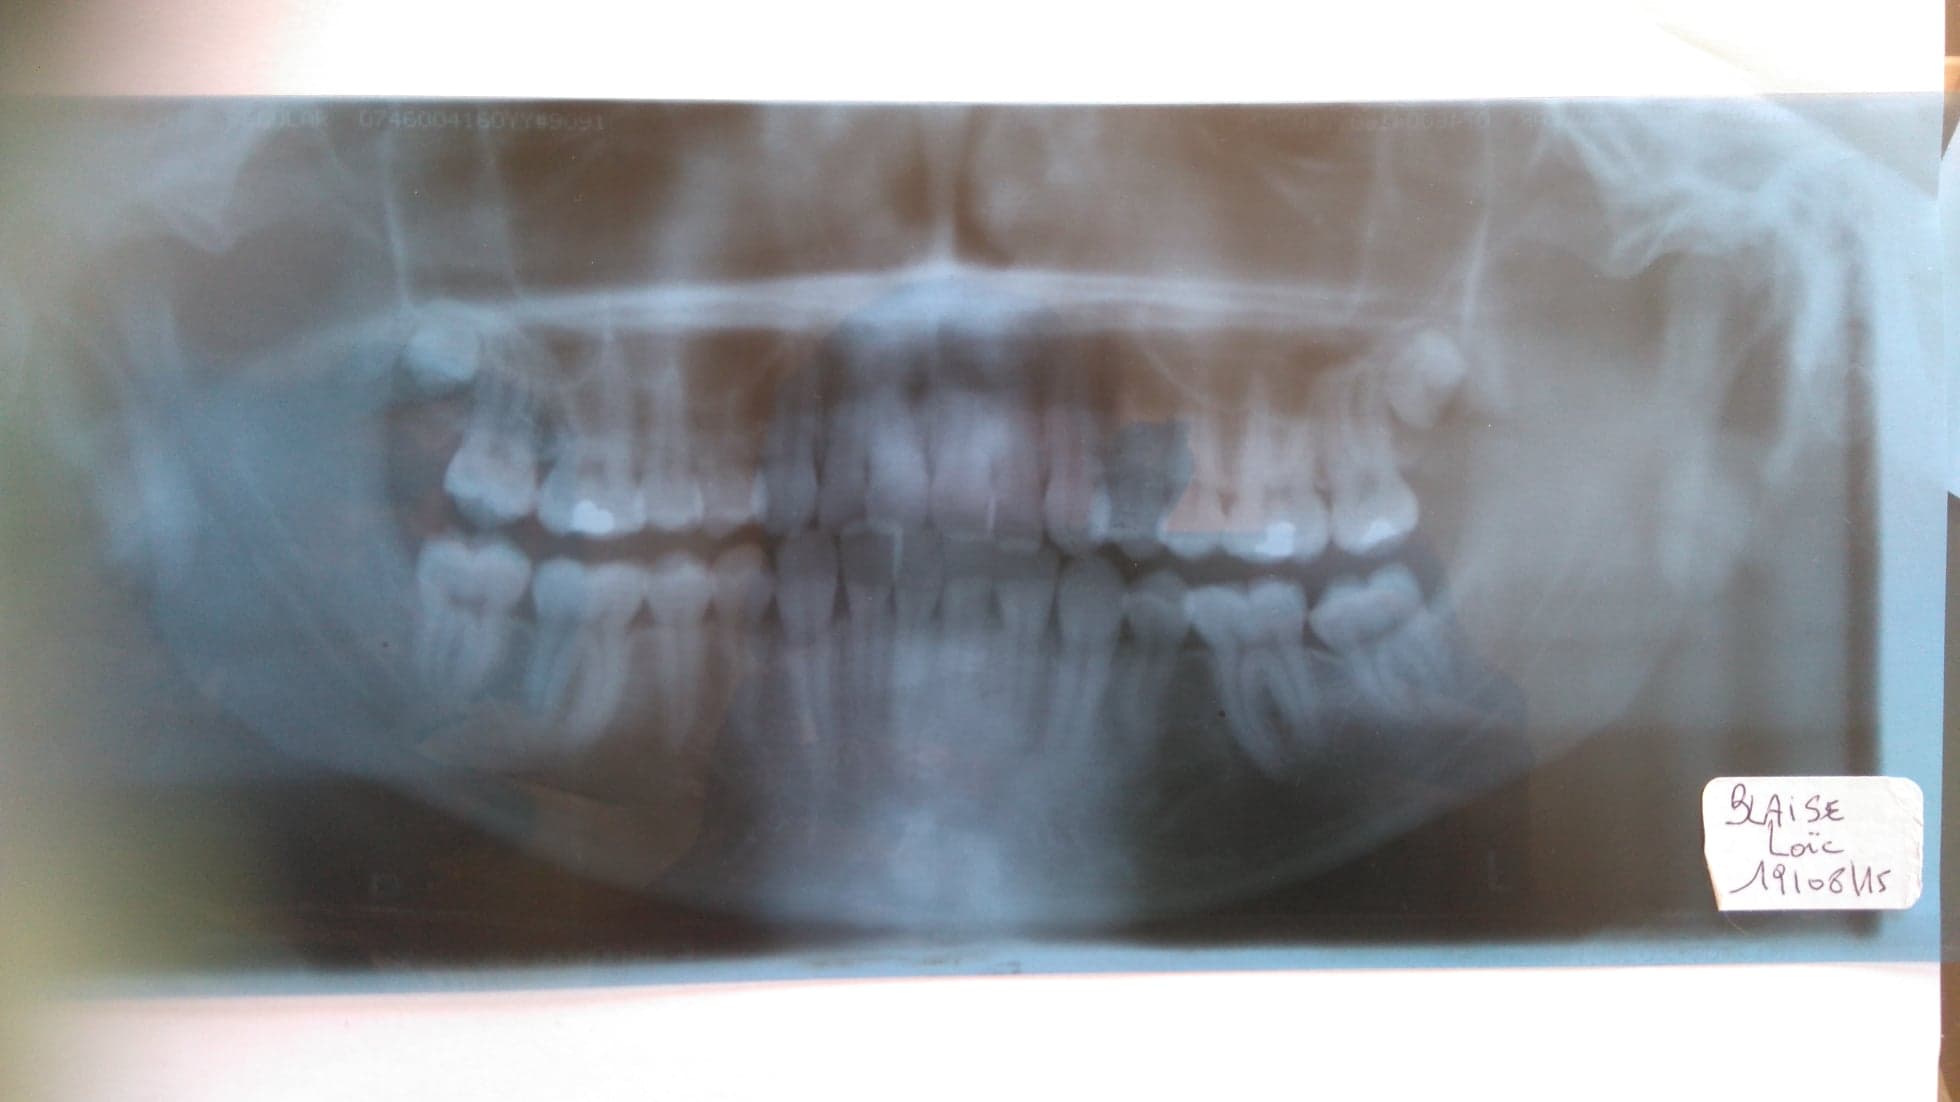

Envoie moi ta dernière radio panoramique pour voir si je peux t’aider

Je met ici mon bilan postural et ma dernière radio des dents.

Bonjour. Il serait peut être intéressant savoir une panoramique plus récente

Oui Pier , je demanderai le 31 pour faire une nouvelle radio et je reviendrai vers vous avec celle ci. pour avoir vos avis.